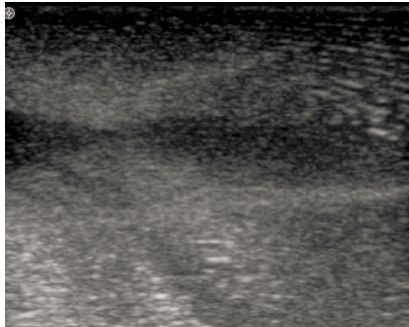

Prime 最基本的应用为检测血液灌流(如图5)、检测微循环、辅助计算血流、心肌灌注等高灵敏度需求的诊断过程。使用微气泡造影剂可提升深层组织的回散信号强度,进而有效延伸超声波系统的成像深度。

图5使用USphereTM小鼠腹部血液灌流检测结果(Vevo2100小动物超声成像仪)

Figure 5. Detection of blood perfusion of the mice abdomen